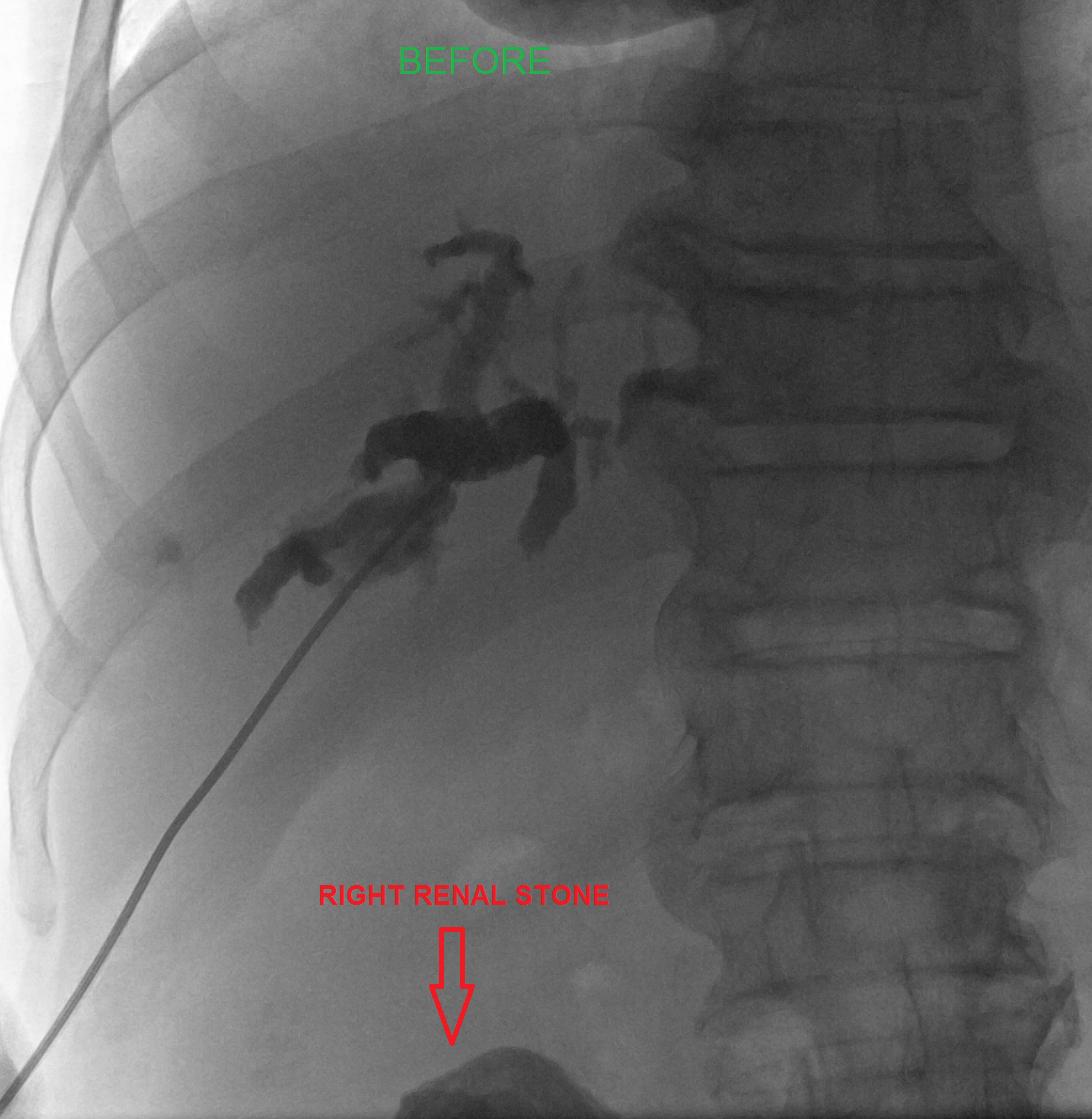

I'm obsessed with papillary lesions of the pancreatobiliary tract these days :D beautiful case of intraductal papillary neoplasm of cbd. No invasion.

#gipath#papillary#biliary pic.twitter.com/p2O4dNwp2J

Prikaži ovu nit -